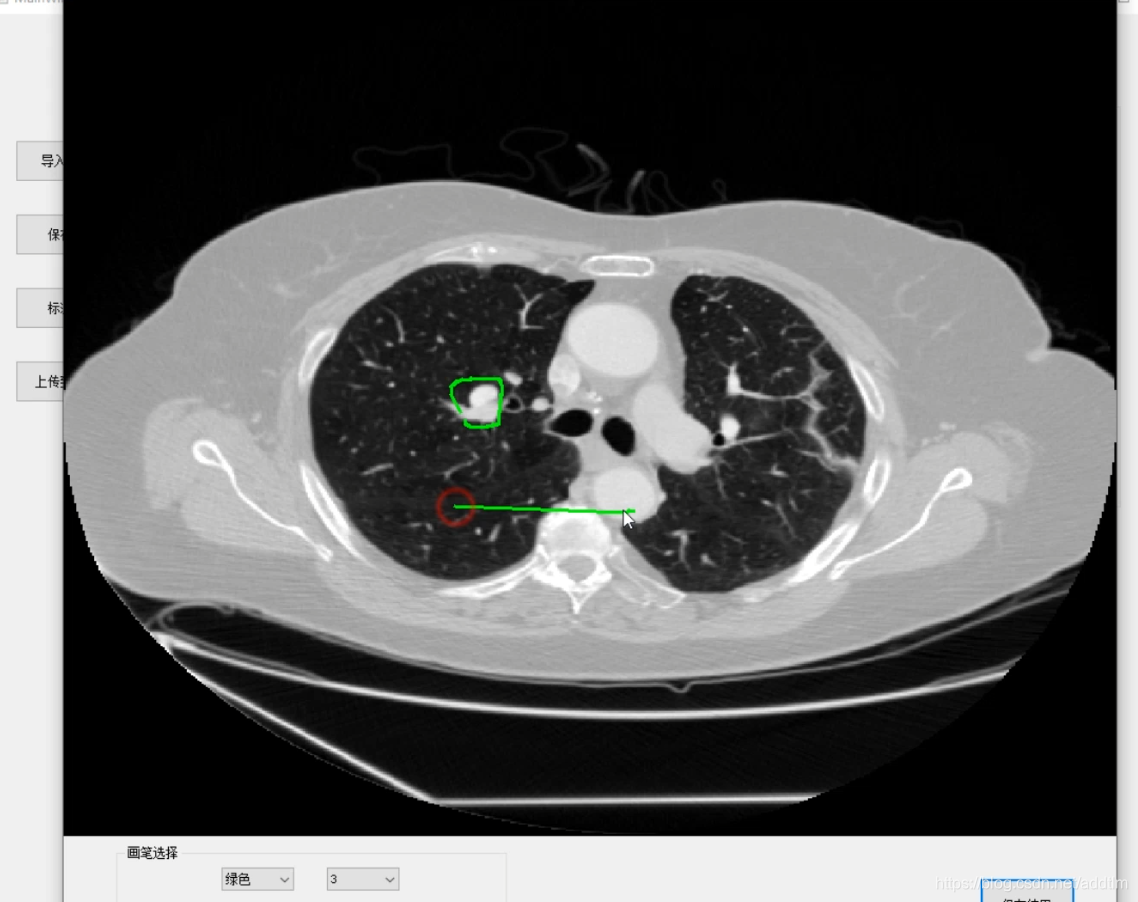

GUI界面大致如下

这两个网络训练达到一定的精度之后,就是GUI的设计和实现,我主要用了pyqt5和designer做了一个简单的界面。